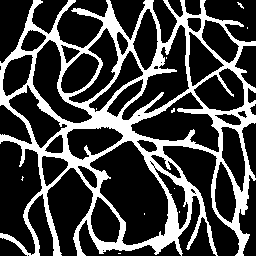

Semantic segmentation of blood vessels is an important task in medical image analysis, but its progress is often hindered by the scarcity of large annotated datasets and the poor generalization of models across different imaging modalities. A key aspect is the tendency of Convolutional Neural Networks (CNNs) to learn texture-based features, which limits their performance when applied to new domains with different visual characteristics. We hypothesize that leveraging geometric priors of vessel shapes, such as their tubular and branching nature, can lead to more robust and data-efficient models. To investigate this, we introduce VessShape, a methodology for generating large-scale 2D synthetic datasets designed to instill a shape bias in segmentation models. VessShape images contain procedurally generated tubular geometries combined with a wide variety of foreground and background textures, encouraging models to learn shape cues rather than textures. We demonstrate that a model pre-trained on VessShape images achieves strong few-shot segmentation performance on two real-world datasets from different domains, requiring only four to ten samples for fine-tuning. Furthermore, the model exhibits notable zero-shot capabilities, effectively segmenting vessels in unseen domains without any target-specific training. Our results indicate that pre-training with a strong shape bias can be an effective strategy to overcome data scarcity and improve model generalization in blood vessel segmentation.